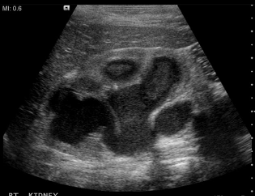

Name this pathology.

Term for a large stone that fills the pelvis and calyces

What is Staghorn calculi?